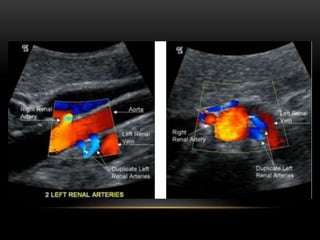

Supernumerary (duplicate) arteries can be seen looking posterior to

the IVC in B Mode and Color in a sagittal plane.

Variant anatomy is common in the renal vascular system. Approximately 30% of

individuals have more than a single renal artery on each side. Supernumery

arteries may occur unilaterally or bilaterally.